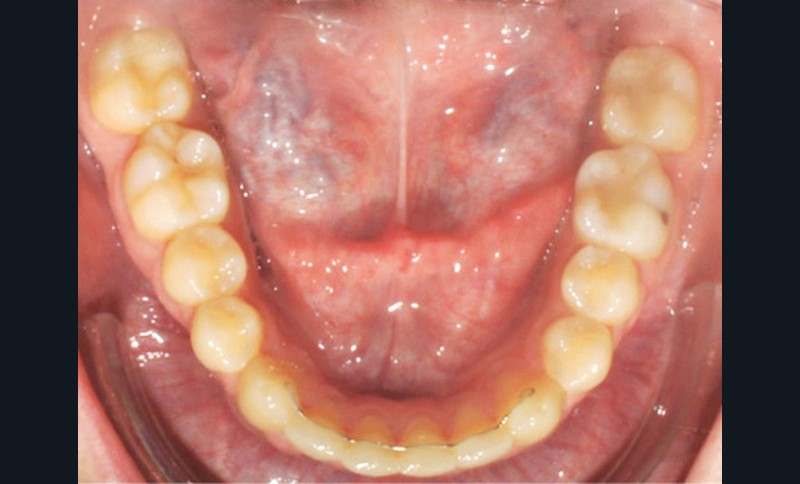

Examen endobuccal (fig. 2a-e)

L’arcade maxillaire est asymétrique, en hémi-lyre droite. Elle présente une mésio-position du secteur 1 en lien avec un encombrement antérieur estimé à 4 mm, se traduisant par une palato-position de la 12 et une rotation de la 11. On observe également des mésio-rotations des premières molaires et une palato-version incisive. L’arcade mandibulaire est ellipsoïde et présente un léger encombrement incisif (1 mm).

Concernant les relations occlusales, on observe une classe II complète subdivision droite. Le surplomb est absent et le recouvrement augmenté, estimé à 4 mm, a provoqué une usure des bords libres de 11 et 21 par attrition. Dans la dimension transversale, on constate une endoalvéolie maxillaire, ainsi qu’une concordance des médianes incisives entre elles, mais toutes deux déviées à droite par rapport au plan sagittal médian.